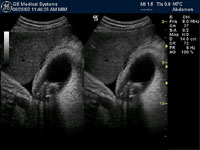

We have modern GE and Aloka ultrasound machines. Ultrasound scans are usually done for the abdominal and pelvic organs. We also perform ultrasound scanning for musculoskeletal problems, testicular, vascular and breast imaging. Trans-vaginal scans are also performed for appropriate cases.

GE gall bladder scan